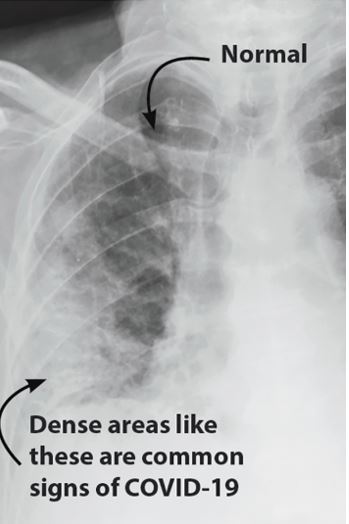

СТ грудног коша

Компјутеризована томографија (СТ) је скуп вишеструких рендгенских снимака. СТ скенер се ротира око тела пацијента и брзо шаље рендгенске зраке кроз тело из различитих углова који се потом обрађују у компјутеру апарата и добијају детаљнe слике танких слојева тела, ширине 0,3 mm и врло често у 3D формату. Код СТ скена грудног коша, што је типично за дијагностификовање COVID-19 инфекције, настаје на стотине слике како би се покрио грудни кош у целости.

СТ скенери су више софистицирани, скупљи и мање доступни у односу на рентген апарате. Теже је вршити њихову деконтаминацију која траје дуже од 20 минута, тврди Пелит. „СТ скенери обезбеђују детаљне информације и самим тиме користе већу количину зрачења него рентген апарати па се користе само када то захтева случај појединачног пацијента.“